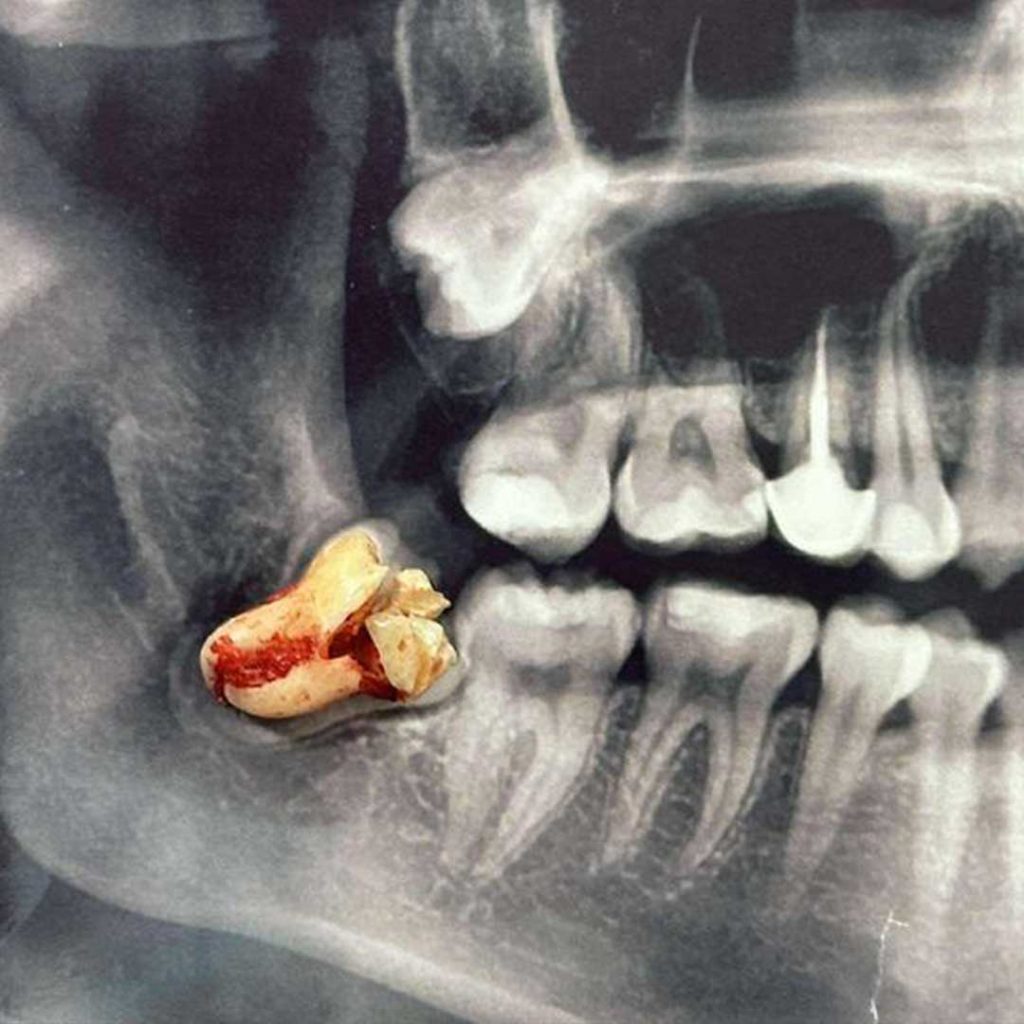

Oral Surgery & Dental Implant Specialists of San Diego

Oral surgery & dental implant specialists of San Diego? Discover the expert care, 3D technology, and patient-first approach at Elevated Oral Surgery.